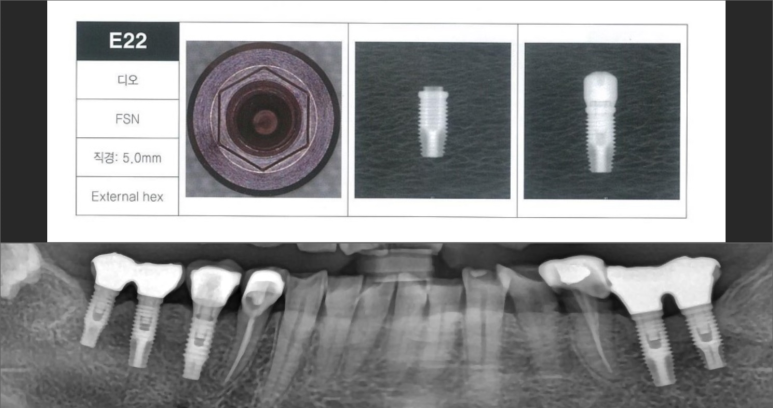

✔ 임플란트 제조사

✔ 제품 규격

✔ 연결 방식

이 정보가 없으면

부품 호환이 어려울 수 있습니다.

👉 엑스레이 + 보철 형태 분석을 통해

제품을 유추할 수 있는 경우가 많습니다.

✔ 국산인지 / 외산인지

이 정도 정보만 있어도 도움이 됩니다.

👉 실제로 정보 없이 내원하신 경우에도

분석 후 교체까지 진행한 케이스가 많습니다.